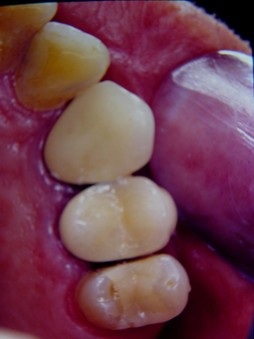

Una vez lograda la erupción forzada y pasado el período de estabilización se retiró la ortodoncia fija (Fig.12 y 13). Se procedió a la preparación de la línea de terminación, a la confección del muñón artificial (plata-paladio) (Fig.14 y 15) y de la prótesis fija de porcelana fundida sobre metal (Fig.16 y 17).

Fig.12 Final de la erucción forzada.

Fig.13 Final de la erucción forzada. Vista lateral

Fig.14 Moñón artificial. Vista lateral

Fig.15 Vista oclusal

Fig.16 Corona definitive. Vista lateral

Fig.17 Vista oclusal

El tiempo del tratamiento ortodóncico fue de 3 meses aproximadamente (fase de tratamiento activo y de estabilización), y los resultados obtenidos fueron monitoreados radiográficamente (Fig.18 y 19).